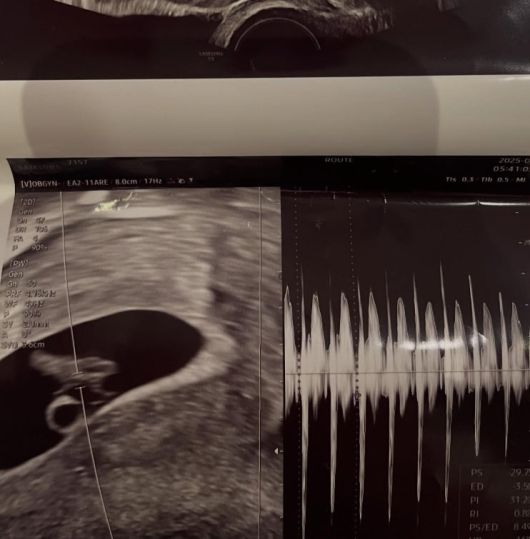

공개된 사진 속 서민재는 일반인 남성과 다정한 스킨십을 하며 럽스타그램을 보였다. 특히 그는 아이의 초음파 사진을 공개하며 팬들의 궁금증을 자아내기도 했다.